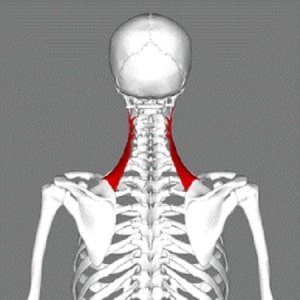

اگر یک شانه بالاتر از دیگری باشد، پس عضلات در طرف این شانه، احتمالاً سفت هستند. دو عضله خاص وجود دارند که این اختلال را ایجاد میکنند.

- آپر تراپزیوس

- اسکاپولا لواتور

عضله آپر تراپزیوس بالاترین قسمت عضلهٔ زیر خود و به طور خاص قسمت نارنجی است. همچنین عضلهای است که هنگام بالا بردن شانههایتان فعال میشود. بنابراین میتوانید تصور کنید که اگر این عضله بیش از حد فعال باشد و در طرف دیگر بسیار سفت باشد، یکی از شانهها را به سمت بالا میبرد.

به همین ترتیب عضله دوم، اسکاپولا لواتور اگر بیش از حد سفت شود، دارای اثر مشابهی است. اسکاپولا لواتور یک عضله است که در پشت ناحیه گوش قرار میگیرد و از پشت گردن به سمت بالای تیغه شانه میرود، در نتیجه قادر به بالا بردن شانه میباشد.

هنگامی که این عضله بیش از حد کوتاه و سفت میشود، یکی از شانهها را بیشتر از آن چه که طبیعی است بالا میبرد.